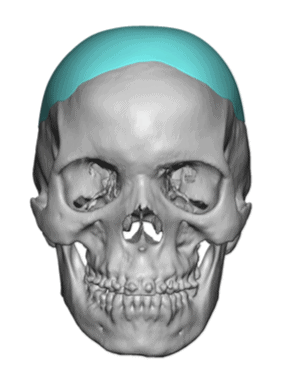

Patient 51

Desire for taller and rounder head shape.

Two stage custom skull implant augmentation technique.

Desire for taller and rounder head shape.

Two stage custom skull implant augmentation technique.